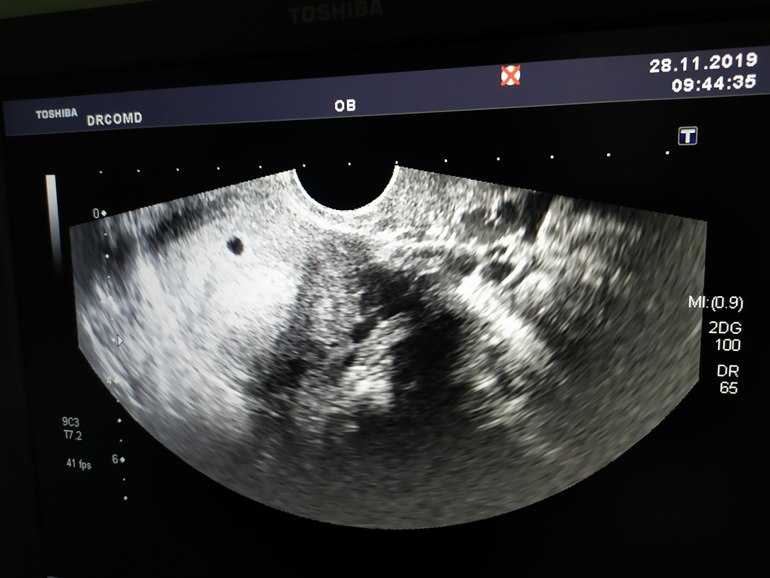

Сегодня была на УЗИ. Акушерская 5н 1д.

ПЯ в матке, 5мм, желточный мешочек 1 мм. Контроль через неделю